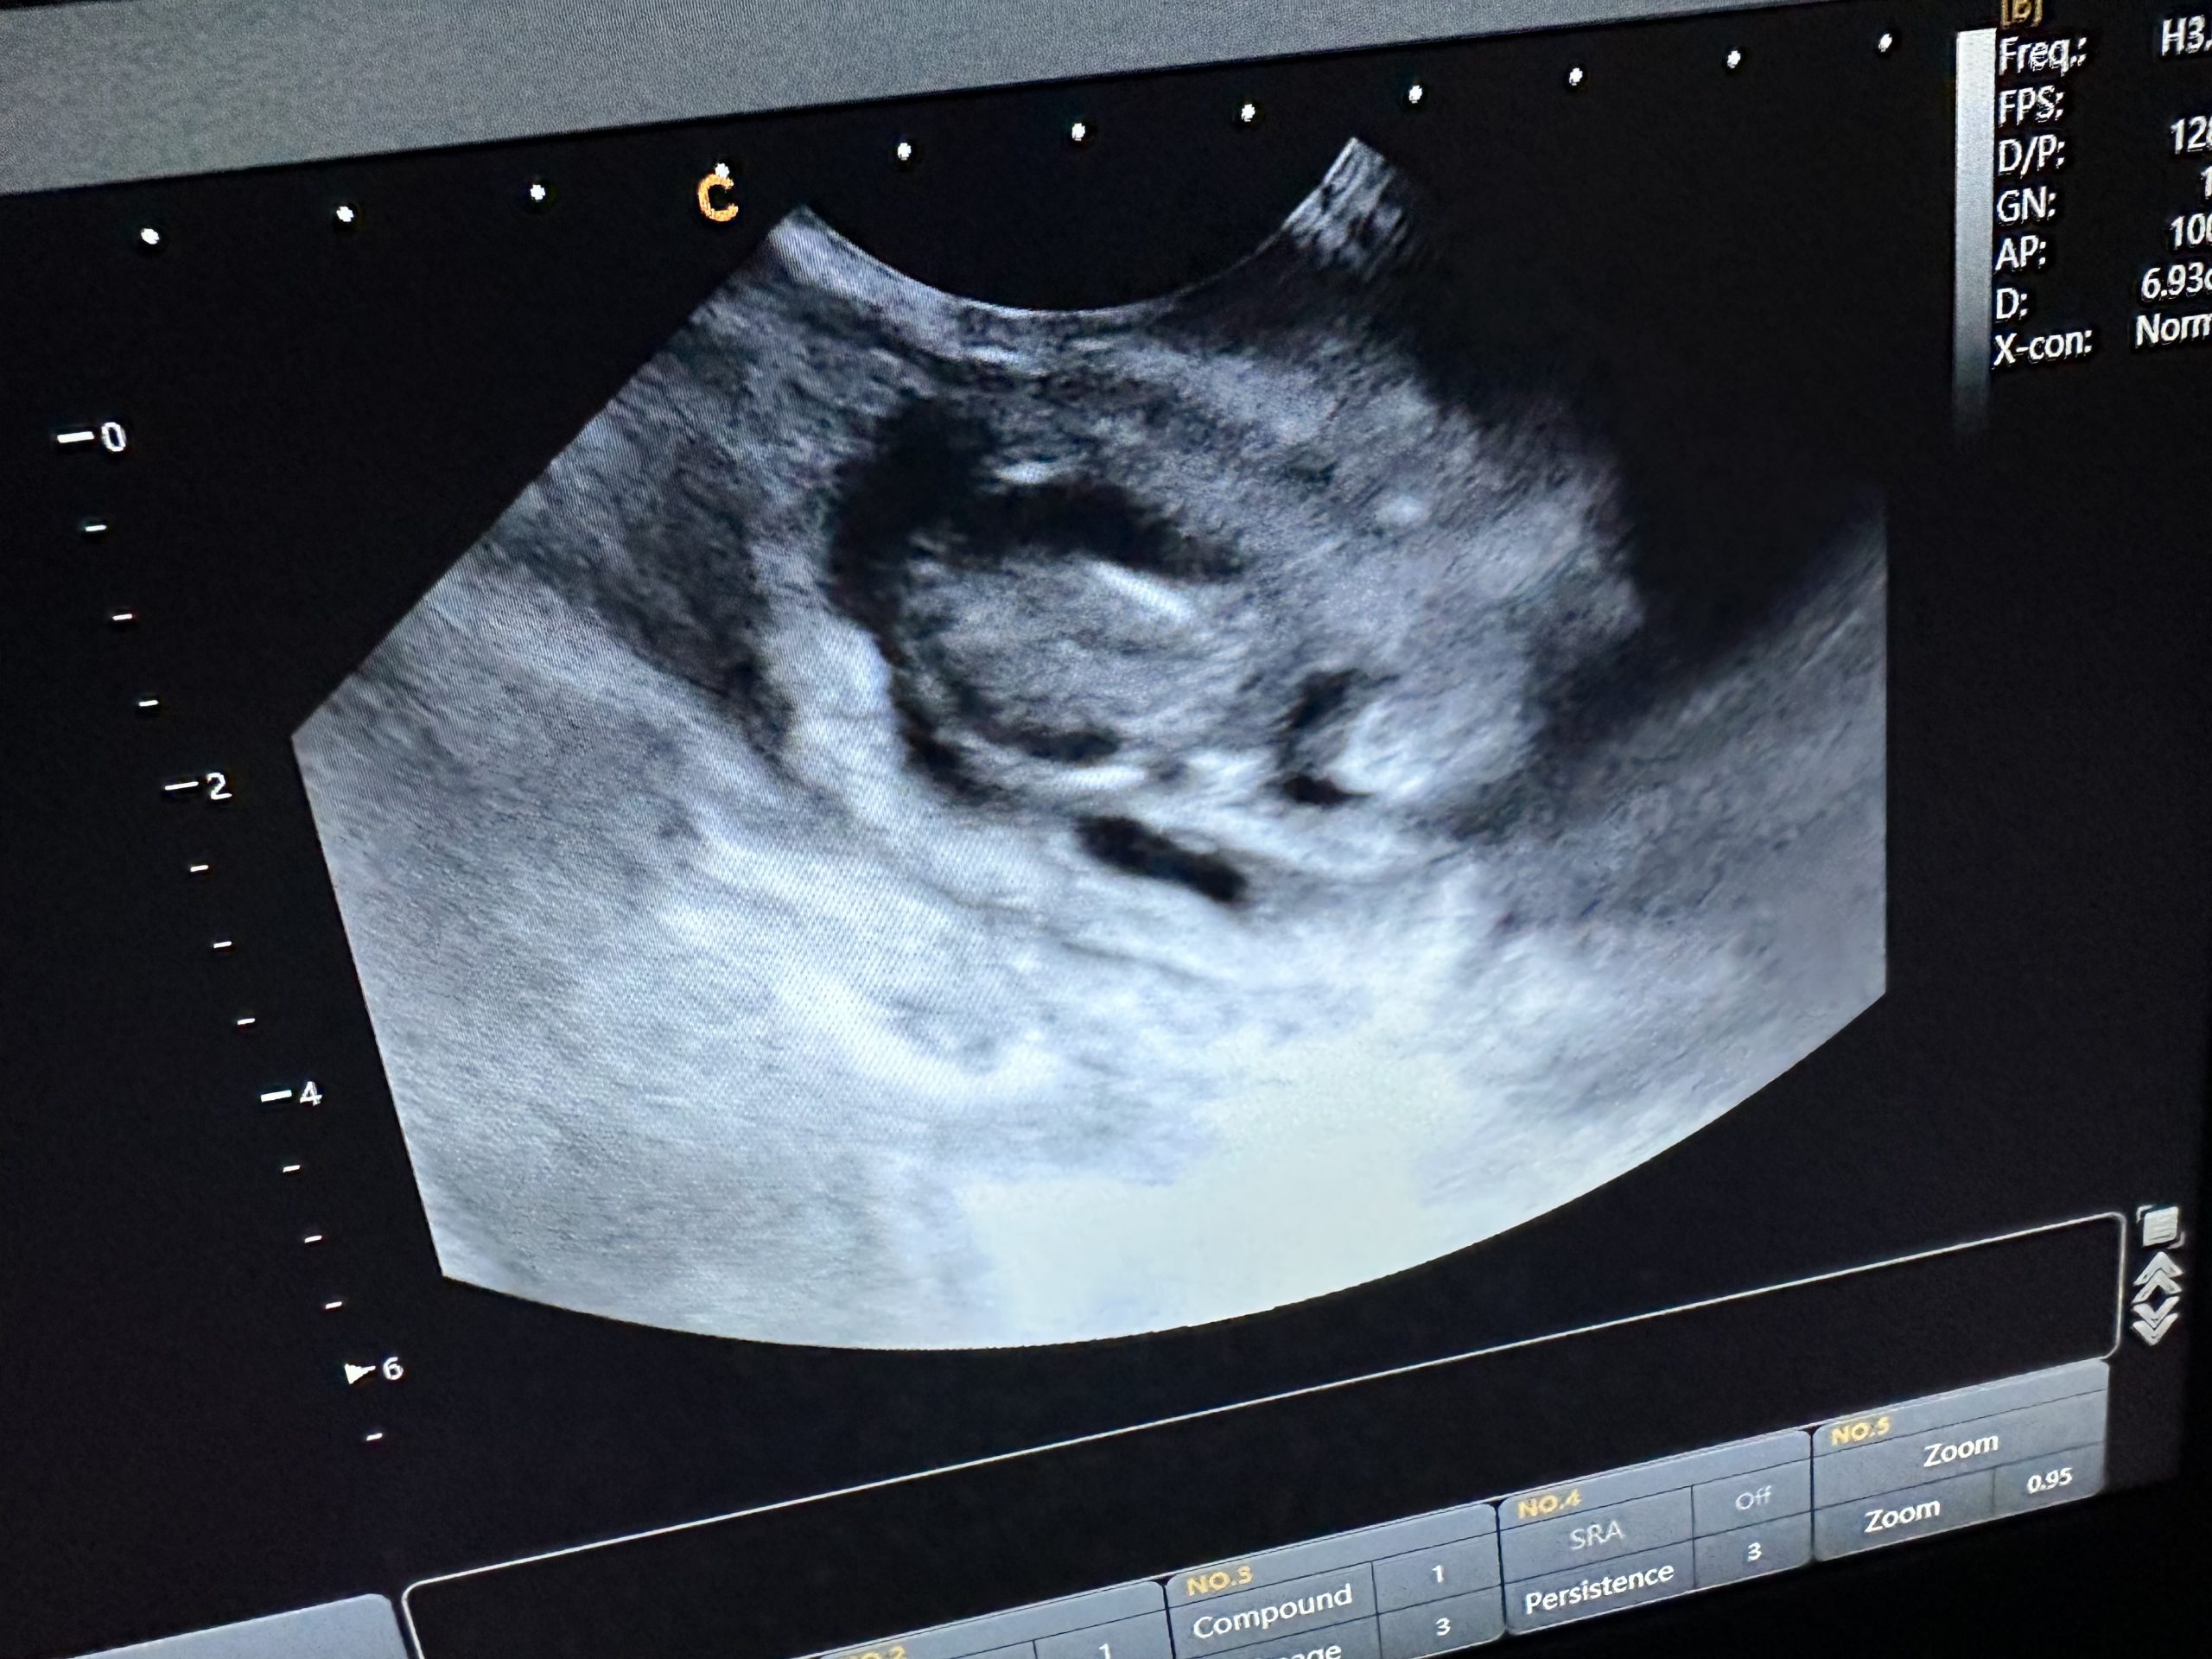

This feline scan was performed at 52 days following a 30 day scan suggesting a singleton kitten. The linear probe was used. The mother delivered the kitten without issue.